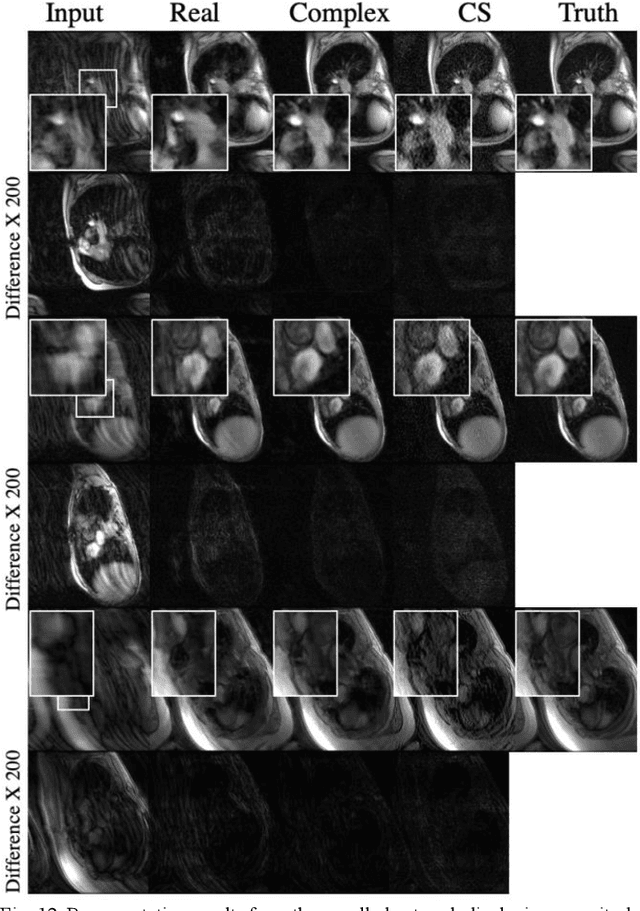

Abstract:Deep learning-based image reconstruction methods have achieved promising results across multiple MRI applications. However, most approaches require large-scale fully-sampled ground truth data for supervised training. Acquiring fully-sampled data is often either difficult or impossible, particularly for dynamic contrast enhancement (DCE), 3D cardiac cine, and 4D flow. We present a deep learning framework for MRI reconstruction without any fully-sampled data using generative adversarial networks. We test the proposed method in two scenarios: retrospectively undersampled fast spin echo knee exams and prospectively undersampled abdominal DCE. The method recovers more anatomical structure compared to conventional methods.

Abstract:Many real-world signal sources are complex-valued, having real and imaginary components. However, the vast majority of existing deep learning platforms and network architectures do not support the use of complex-valued data. MRI data is inherently complex-valued, so existing approaches discard the richer algebraic structure of the complex data. In this work, we investigate end-to-end complex-valued convolutional neural networks - specifically, for image reconstruction in lieu of two-channel real-valued networks. We apply this to magnetic resonance imaging reconstruction for the purpose of accelerating scan times and determine the performance of various promising complex-valued activation functions. We find that complex-valued CNNs with complex-valued convolutions provide superior reconstructions compared to real-valued convolutions with the same number of trainable parameters, over a variety of network architectures and datasets.